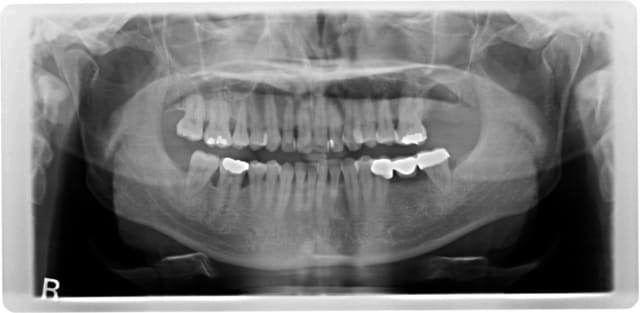

la pano comme promis un bel exemple de massacre

avec tout ce nonos dessous et les surcontours pffff

Ceci dit comme il a un bridge en face il peut rester sans sa 7.

Sois sympa regardes un peu ce qui se passe au niveau de la poche en distal de 37 ou espères-tu lui coller deux implants ?

Allez! Pleure pas et fais vite en bas à droite, la 46 a des pb imminents...